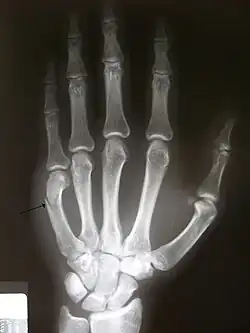

Pain is most commonly experienced through a burn, laceration, or blunt force trauma to the human tissue, bone, or internal organs (Vogt, 2005). Pain is a strong motivator for individuals to withdraw from dangerous environments, by protecting a damaged area while it heals. Pain is an important response as it creates associative learning to avoid similar experiences in the future (Lumley et al., 2011). Common sensations involve feelings of burning, aching, freezing, nausea, stinging, and crunching to name a few. Often injuries such as laceration, burning, bites, fracturing, or blunt force trauma to the human tissue are the most common forms of injury (Vogt, 2005).